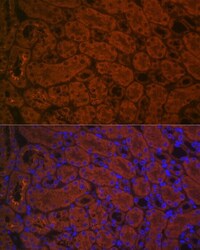

- Submitted by

- Invitrogen Antibodies (provider)

- Main image

- Experimental details

- Immunohistochemistry (Immunofluorescence) analysis of ACE2 in rat kidney. Samples were incubated with ACE2 Polyclonal antibody (Product # PA5-88732) using a dilution of 1:100 (40x lens). Blue: DAPI for nuclear staining.